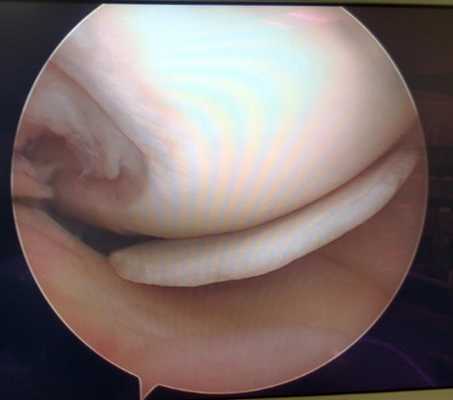

Удалённый фрагмент внутреннего мениска при разрыве по типу ручки лейки с блоком коленного сустава.

Мениск после обработки по поводу паракапсулярного субтотального разрыва по типу ручки лейки.